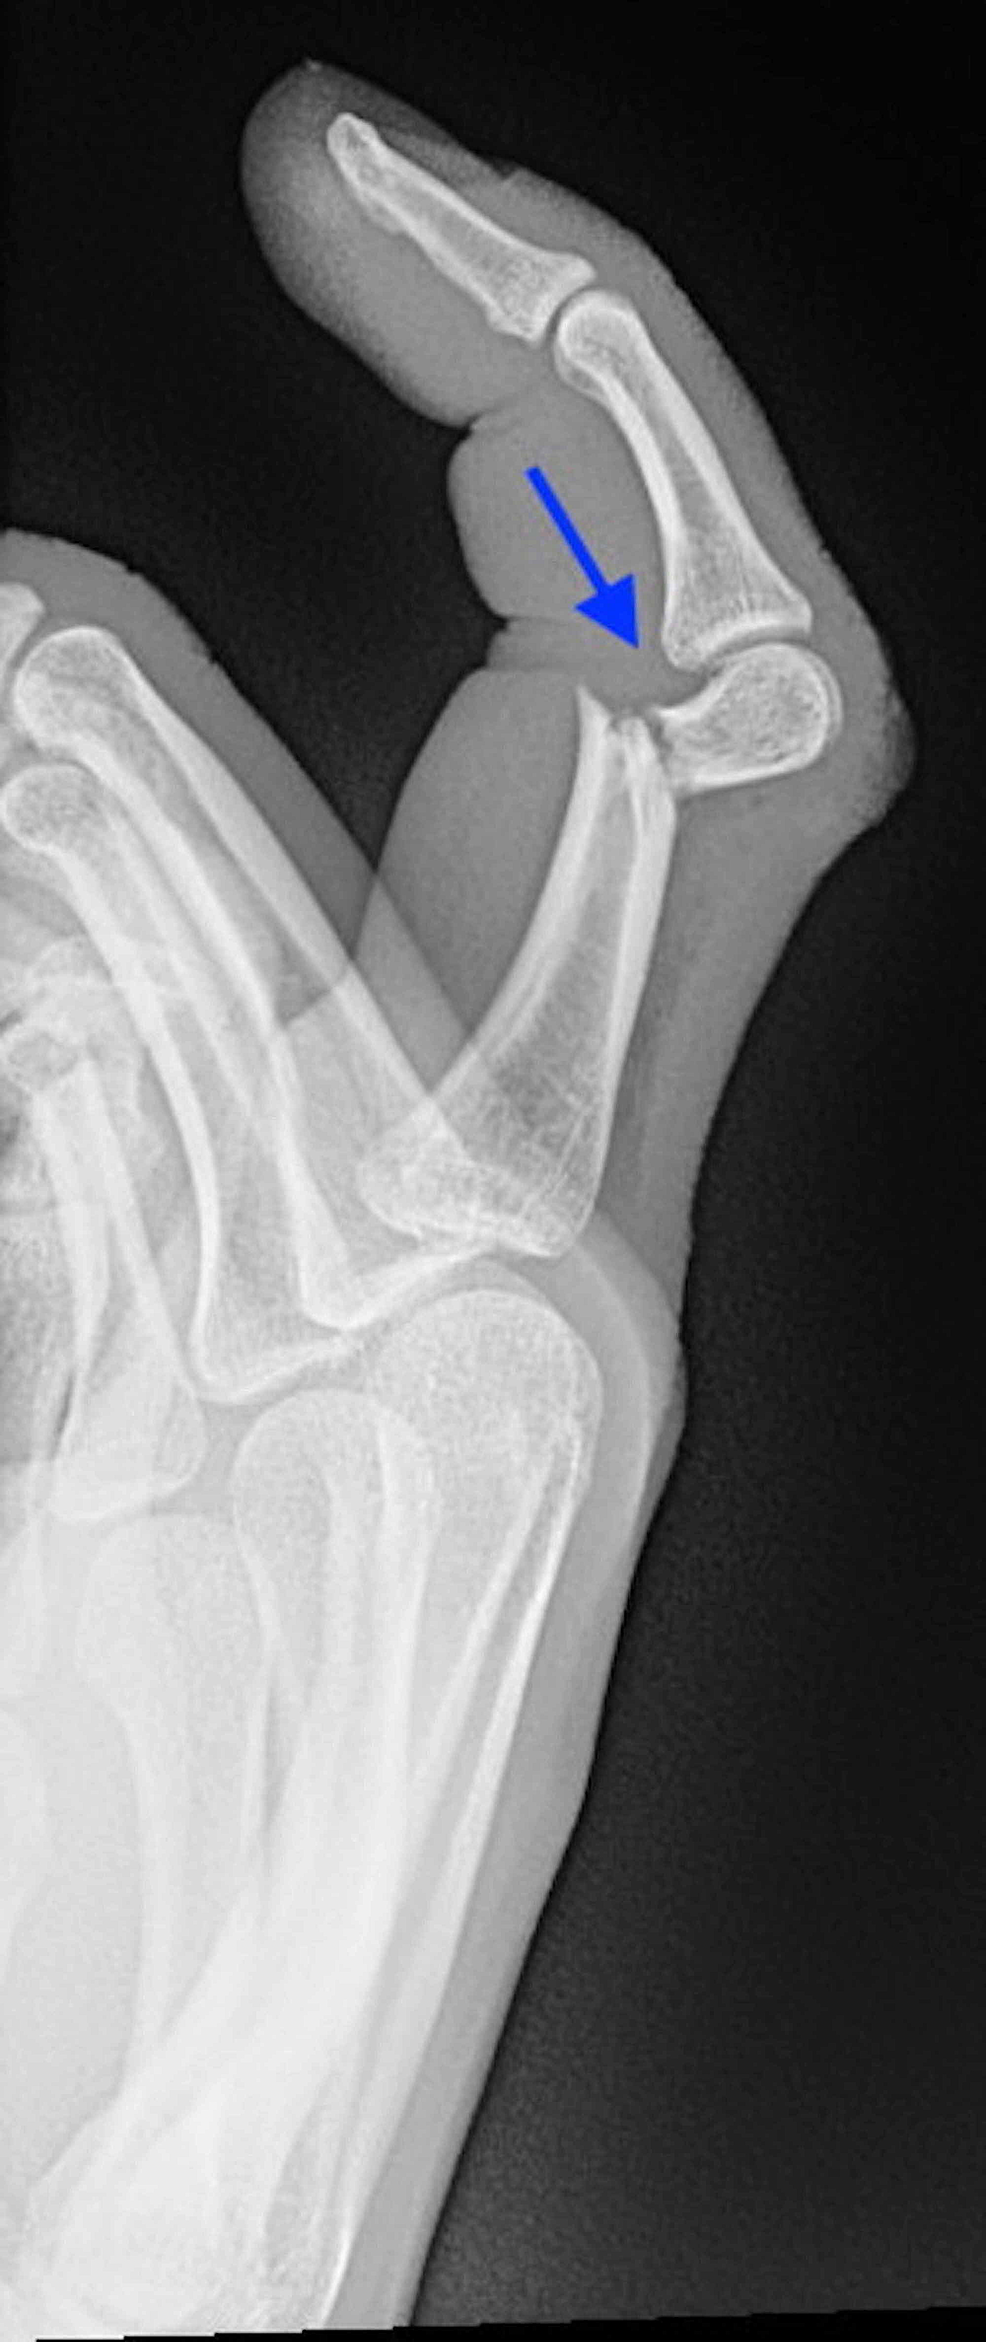

발가락 골절 수술 치료

- 적용 시기: 복합 골절, 압박 골절, 뼈 조각이 여러 개로 나뉜 경우처럼 깁스나 스플린트만으로 회복이 어려운 경우.

- 회복 기간: 수술 후에도 2~4주 이상의 안정기가 필요하며, 이후에는 재활 운동이 필수로 따라옵니다.

- 치료 방식: 핀을 박거나 금속판을 대는 방법을 사용합니다. 골절 부위를 정확히 정렬하고 뼈가 잘못 붙지 않도록 하는 것이 핵심입니다.

- 핀 고정 수술

- 뼈가 복합적으로 부러지거나, 어긋나서 그대로 붙으면 기능에 치명적 문제가 예상되는 경우에는 핀이나 금속판을 삽입하는 수술을 진행합니다.

- 수술 후에는 손가락 움직임을 최소화하고, 적절한 시점에 재활 운동을 시작해야 합니다.